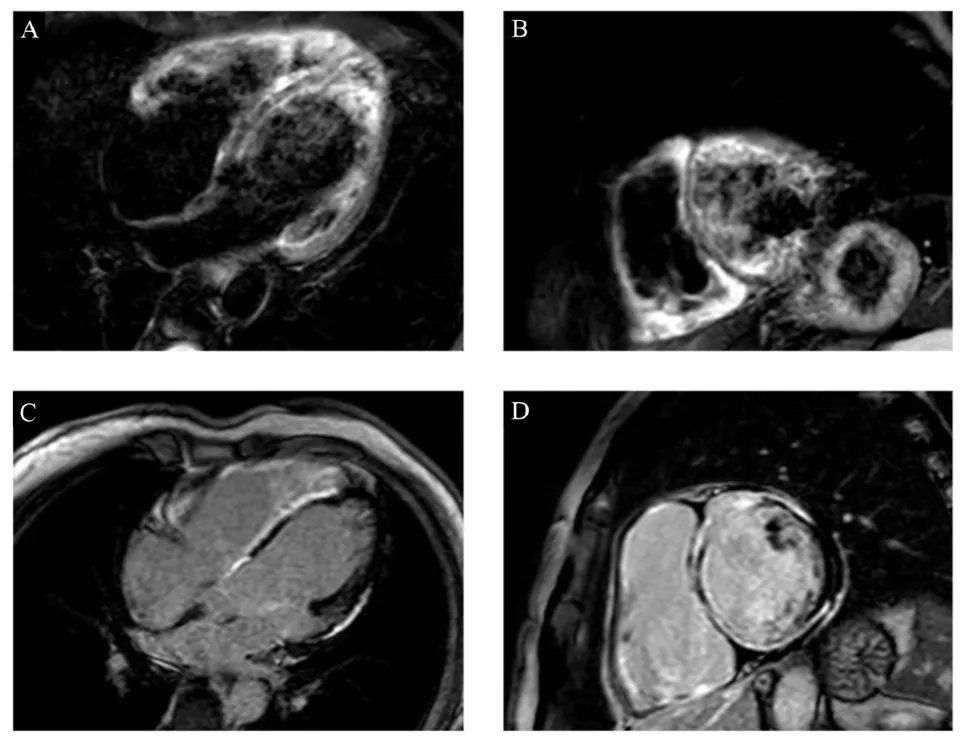

🫀 RISCONTRO OCCASIONALE DI TROMBO IN AURICOLA ATRIALE DESTRA IN UN GIOVANE PAZIENTE CON SCOMPENSO CARDIACO CONGESTIZIO E IN RITMO SINUSALE🫀